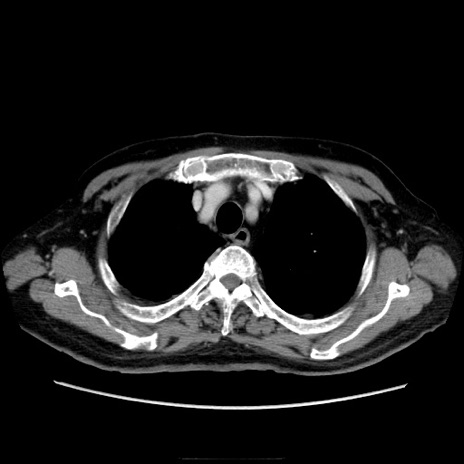

冠状断像